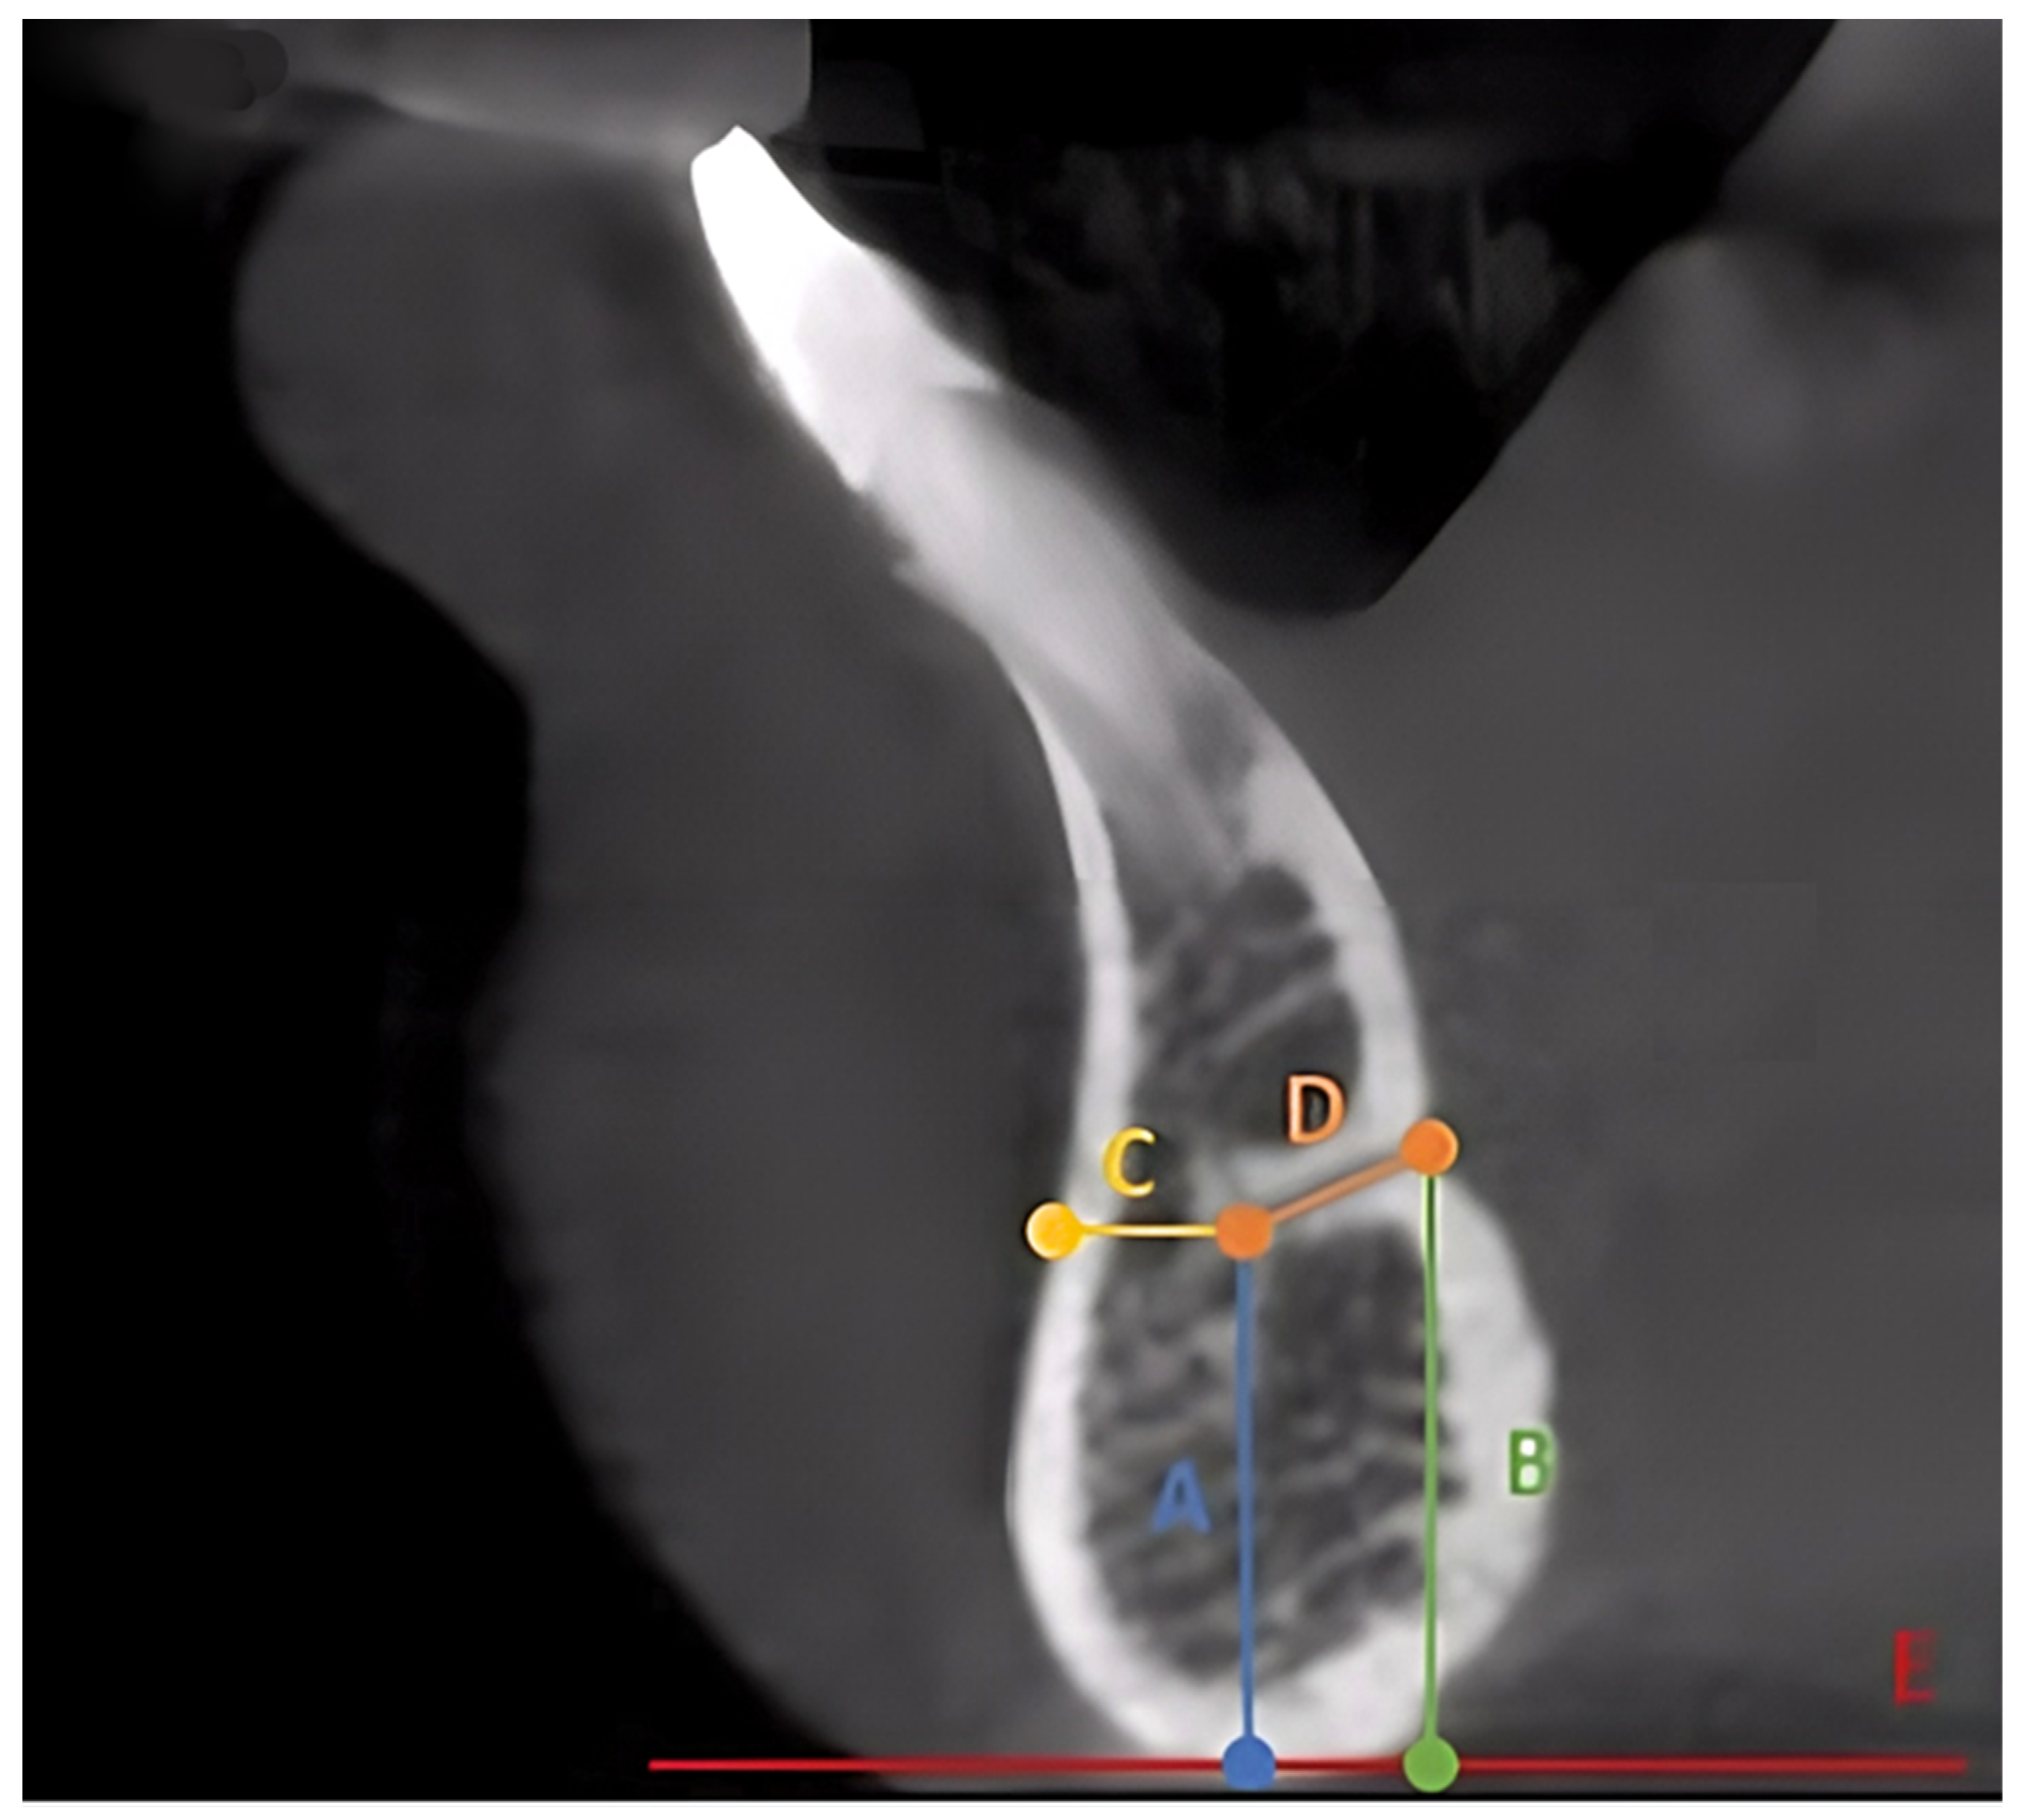

2.2. Data Collection, Image Reconstruction, and Assessments